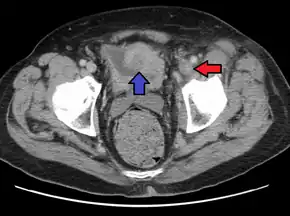

Phlegmasia cerulea dolens (PCD) is a severe form of deep venous thrombosis (DVT) that blocks outflow of blood from a limb.[1] Symptoms include swelling, pain, and bluish discoloration.[1] Most commonly the leg is affected, with less than 10% of cases affected the arm.[2] Complications may include pulmonary embolism, compartment syndrome, gangrene, and limb loss.[1]

It is characterized by progressive lower extremity swelling distal to the thigh, tight shiny skin, bluish skin (inadequate blood oxygenation), petechiae or purpura, and sudden severe pain of the affected limb in proportion to the level of venous blockage. People often have difficulty walking. Bilsters, bullae, numbness, an motor weakness may develop in severe cases, along with gangrene in ~50% of cases.[1][3] Distal pulses may be felt early on but may diminish over time, and doppler signal can be usually heard throughout disease progression.[3] The left limb is more commonly affected due to its vascular anatomy (the right internal iliac artery directly overlies the left iliac vein).[4][1]